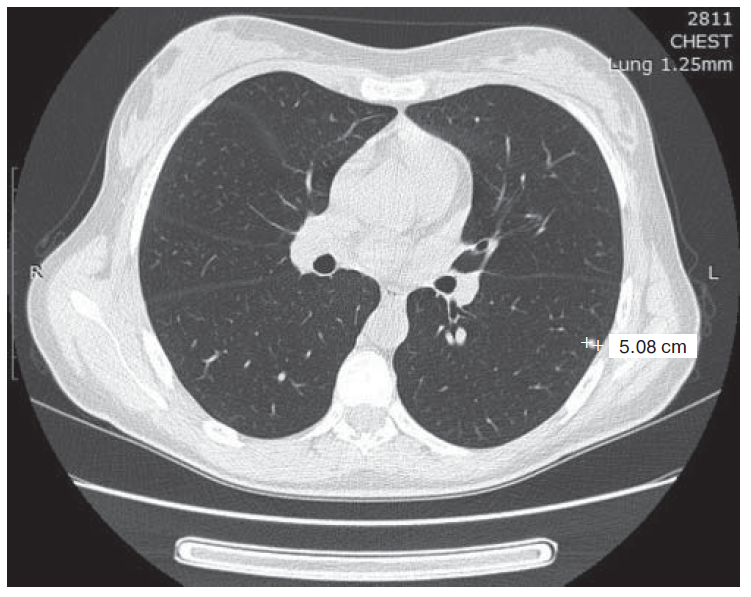

3. Fig. 2. Computer tomography of thoracic organs cavities: tumor formation in S6 of the left lung 5 × 4 mm in size. | |